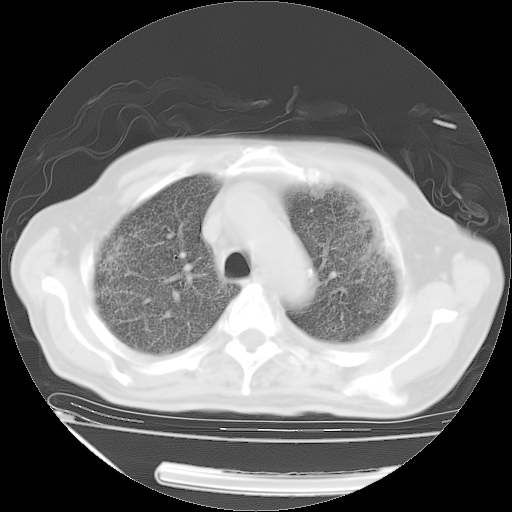

甲强龙80mg/日+抗结核治疗(异烟肼+利福霉素+乙胺丁醇)10天。复查肺部CT。

治疗10天肺部CT